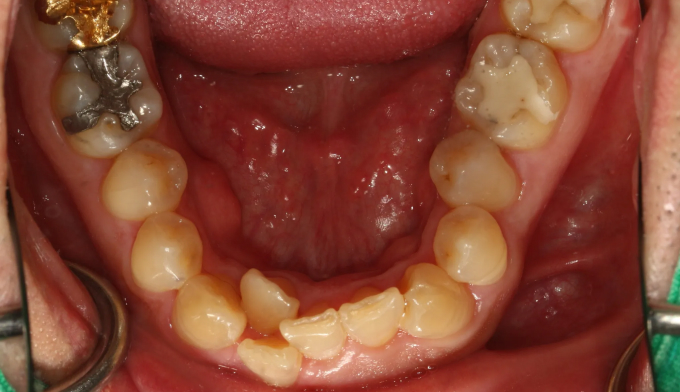

앞니에 치아를 배열할 공간이 부족해 보입니다. 또한 과도한 교합력으로 인해 아래 앞니가 거의 안보이는 과개교합이 관찰되며, 해당 부위의 뼈도 웃자라 있는 골융기가 관찰됩니다.